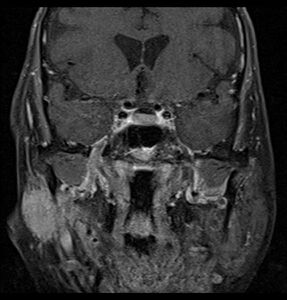

Primary treatment for this cancer, regardless of body site, is surgical removal with clean margins. This surgery can prove challenging in the head and neck region due to this tumor's tendency to show a perineural discontinuous growth, meaning that it follows nerves and different "nests" of the tumor can exist without a connection to the original tumor. Therefore, MRI-images should be analysed following nerve tracts up to the brainstem. Adjuvant or palliative radiotherapy is commonly given following surgery. For advanced major and minor salivary gland tumors that are inoperable, recurrent, or exhibit gross residual disease after surgery, fast neutron therapy is widely regarded as the most effective form of treatment.[13][14][15][16] Chemotherapy is used for metastatic disease. Chemotherapy is considered on a case-by-case basis, as data on the positive effects of chemotherapy are limited. Clinical studies are ongoing, however.[citation needed]

Coronal MRI showing right parotid adenoid cystic carcinoma with perineural spread of tumor: The tumor originates in the right parotid gland and spreads along the trigeminal nerve via the auricuotemporal branch extending intracranially through the foramen ovale at the skull base towards Meckel's cave.